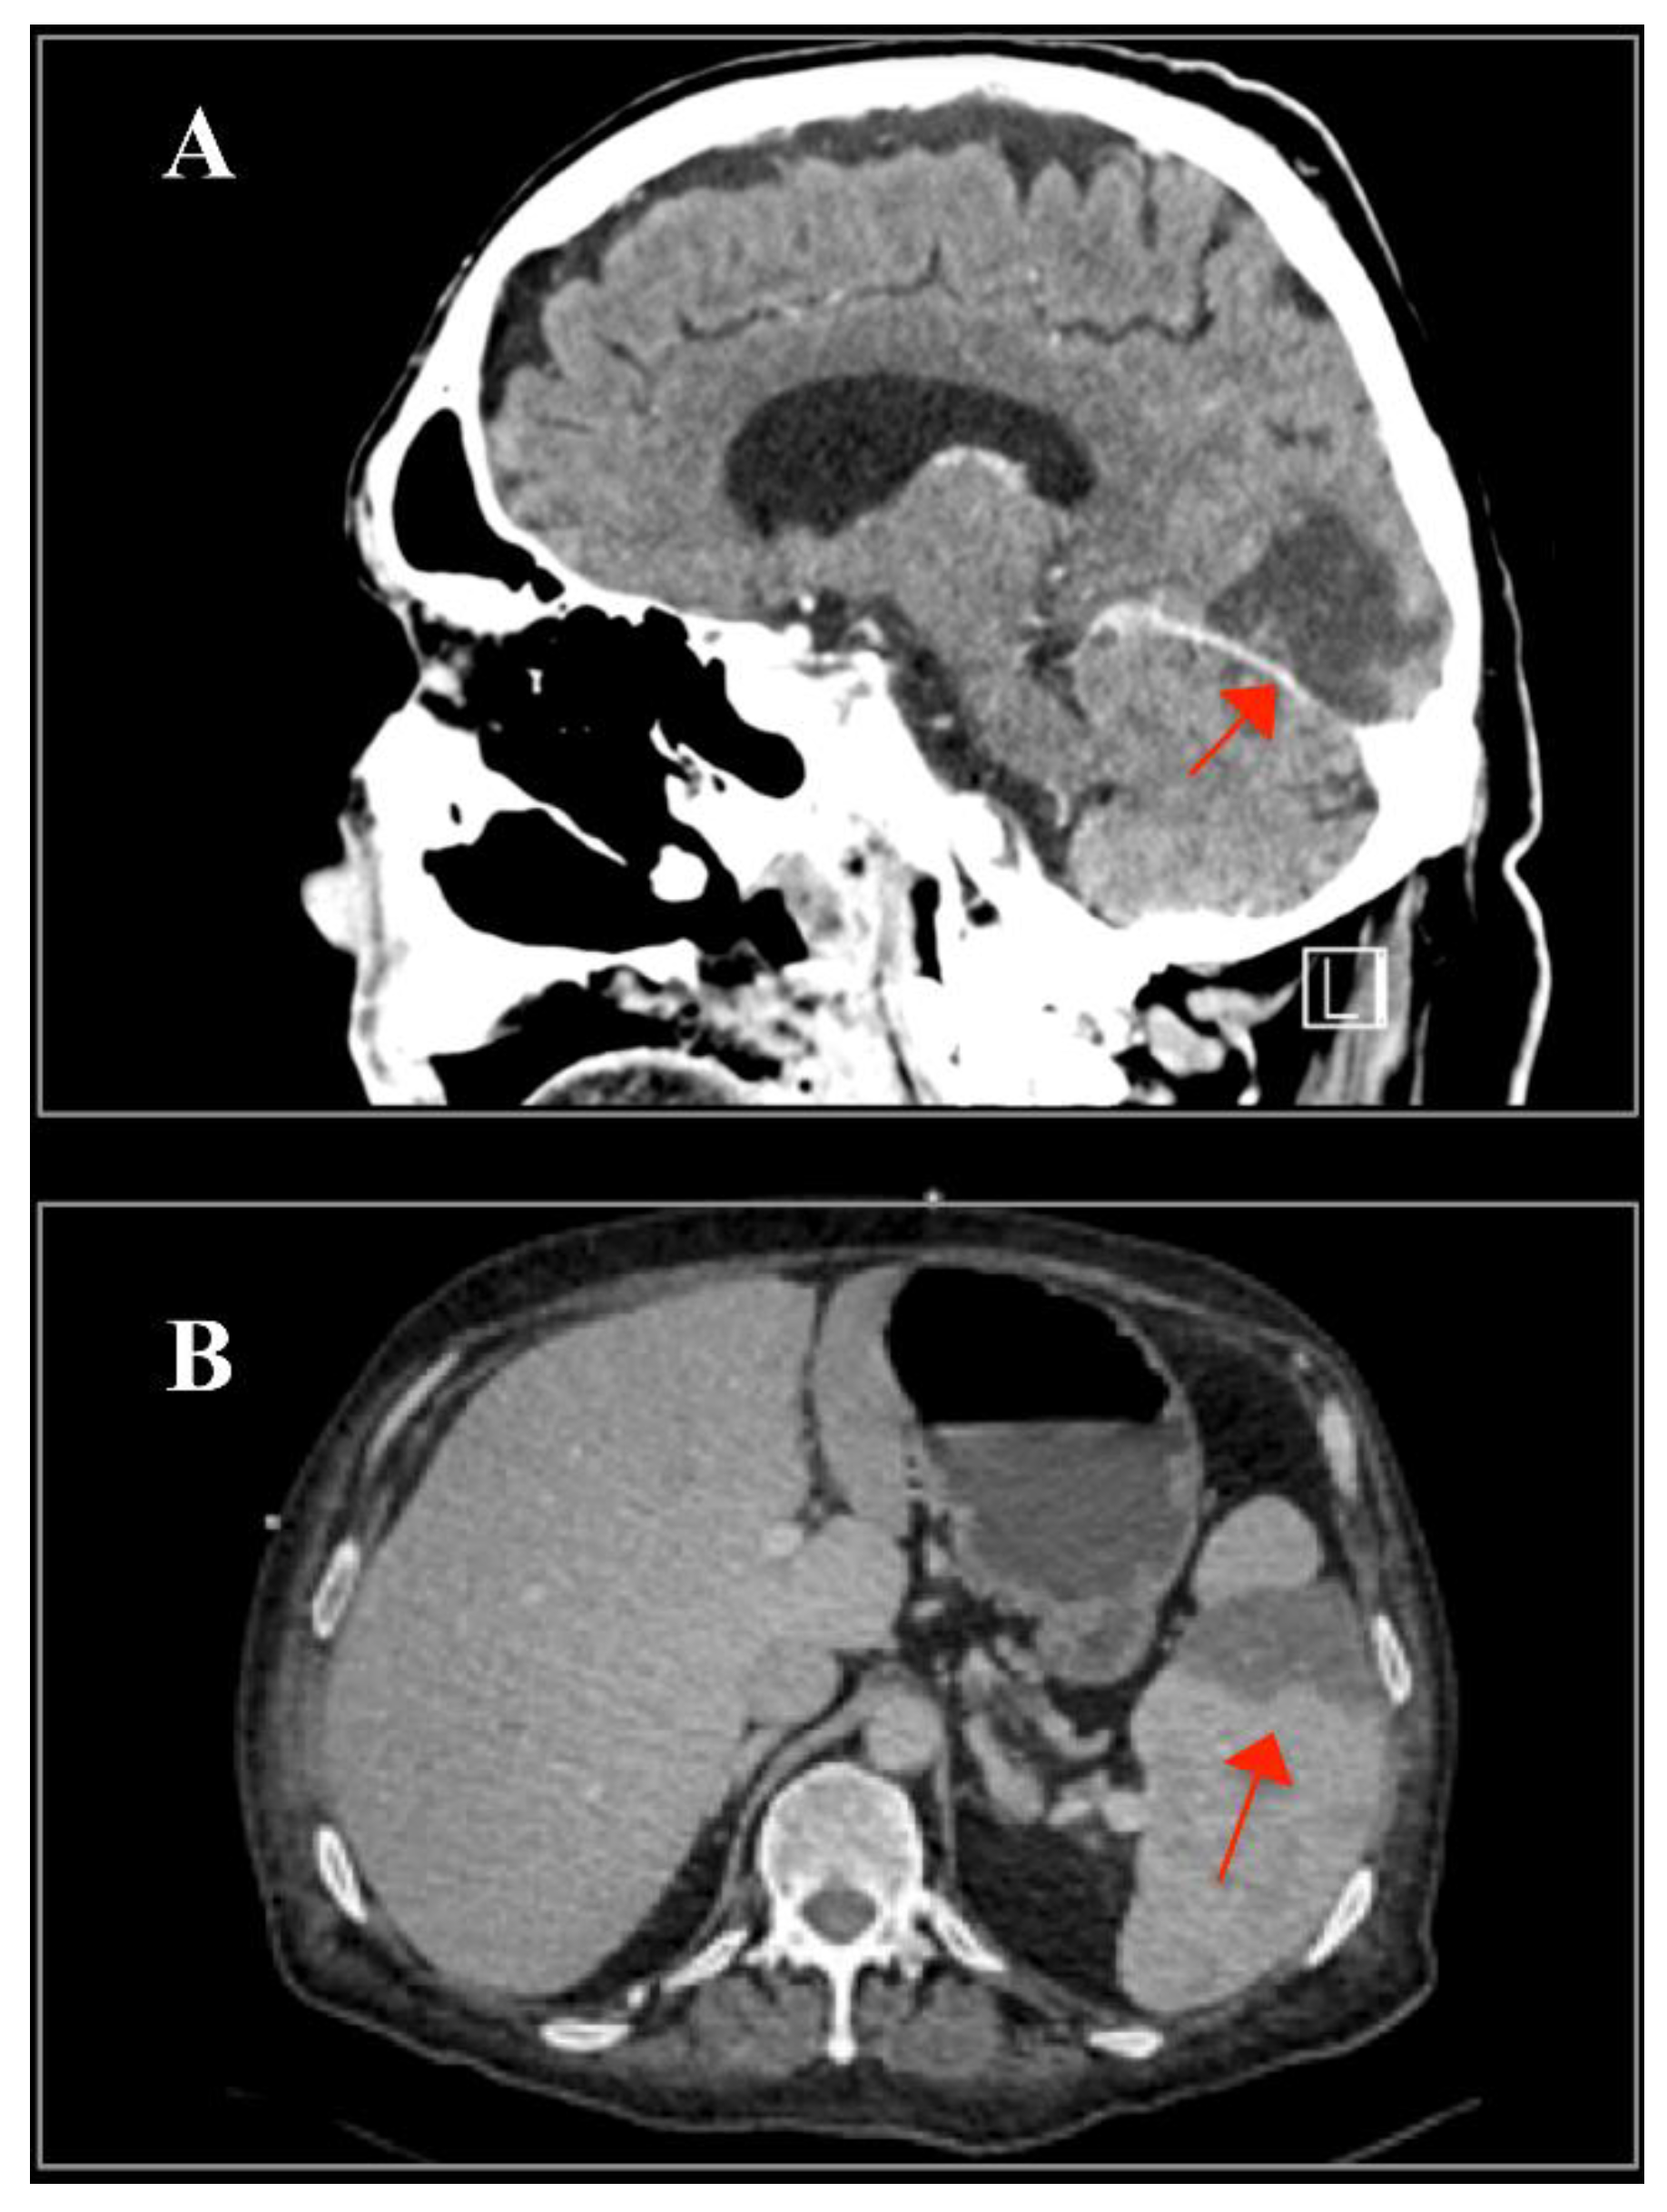

There was a subacute right occipital stroke and splenomegaly with splenic infarctions, both of which were interpreted as embolic consequences of the IE (Figure 4).

Figure 4. (A) Cerebral computed tomography (CT) demonstrating subacute right occipital stroke (arrow) and (B) abdominal CT showing one of the splenic infarctions (arrow).